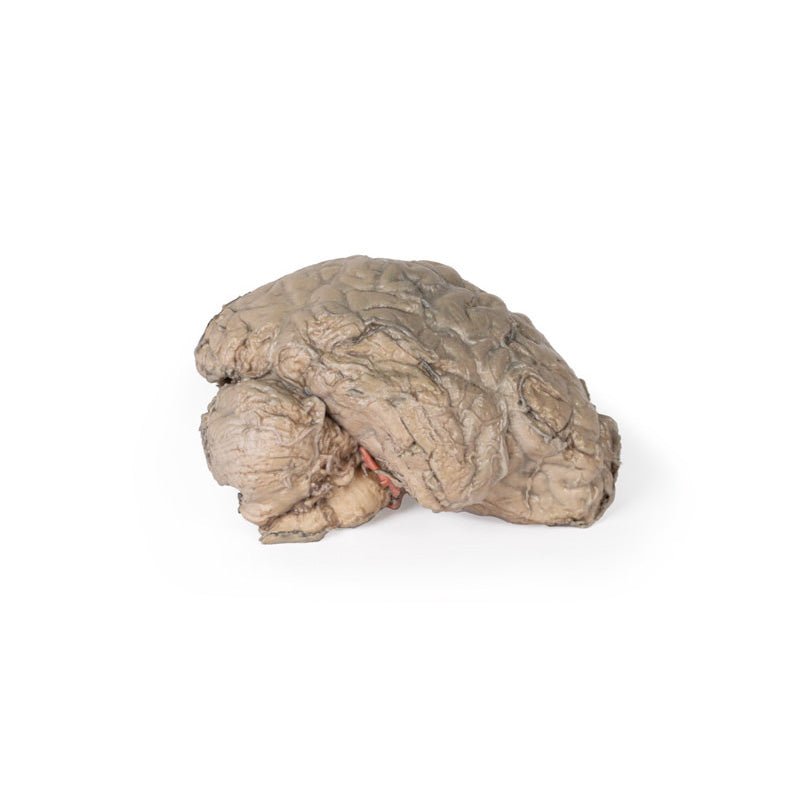

This 3D model is a midsagittal hemisection through a whole brain, preserving the right side anatomy and deep brain

structures and spaces visible in the midline. In lateral view, the right cerebral and cerebellar hemispheres are

covered in the arachnoid mater. In the midline view, the brain regions from the cerebrum to the medulla oblongata